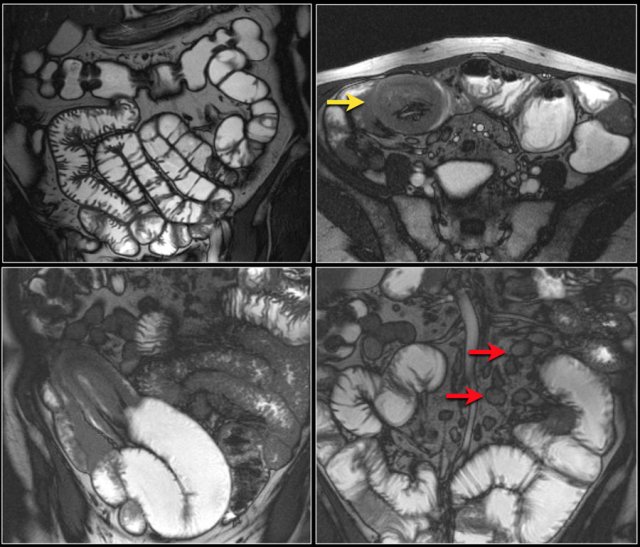

Here a typical lymphoma presenting as a large thick walled mass in the proximal jejunum with FDG uptake.

Dilated lumen at the site of the mass and prestenotic dilatation of the duodenum (red arrow)

First study the images and take special notice of the first image.

Then continue reading.

The findings are:

- Reversed fold pattern indicating celiac disease

- Ileal-ileal intussusception (yellow arrow), in a patient with multifocal small bowel lymphoma (not all lesions shown here).

- Mesenteric lymphadenopathy (red arrows).

EATL

Here another patient with celiac disease.

There is an irregular mass in the jejunum with luminal dilatation.

There is infiltration of the mesentery.

Pathology showed a T-cell lymphoma in celiac disease.

This is called enteropathy associated T-cell lymphoma or EATL.

This is a type of T-cell lymphoma that affects the small intestine in patients with celiac disease.

Here another example of a T-cell lymphoma in celiac disease.